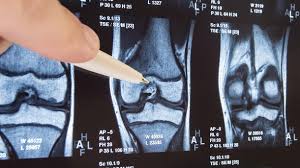

Ingwer ist in der Lage ein bestimmtes Enzym im Körper zu hemmen das bei Arthrose Schmerzen hervorrufen kann. Arthrose tritt allerdings immer häufiger bei jungen Menschen auf. AndreyPopov iStock Als Kniearthrose Gonarthrose bezeichnet man den fortschreitenden Gelenkverschleiß im Kniegelenk. Dabei kommen Physiotherapie physikalische Behandlungen wie unter anderem. Das Ziel der Behandlung mit Medikamenten ist es die Symptome der Kniegelenksarthrose zu beseitigen. Sie sind in Form. Viele Studien belegen dass gezielte Bewegung und Kräftigung sowohl die Muskulatur stärkt als auch die Gelenkfunktion verbessert und das Wohlbefinden steigert. Stimmt zwischen ihnen die Balance. Pharmakologische Behandlung bei Kniearthrose Hilfe aus der Apotheke.

Physiotherapie und Sport verbessern die Gelenkfunktion und reduzieren chronisch e Schmerzen bei Kniearthrose. Unser Körper muss viel aushalten. Das Ziel der Behandlung mit Medikamenten ist es die Symptome der Kniegelenksarthrose zu beseitigen. Konservative Behandlung der Kniearthrose Behandlung der Arthrose-Ursachen ist erfolgversprechender als die Therapie der Beschwerden. In der Bildergalerie finden Sie die 10 besten Tipps für gesunde Gelenke Foto. Beim Treppensteigen so viel Gewicht wie möglich auf dem Treppengeländer abstützen. Muskeln stabilisieren das Knie.